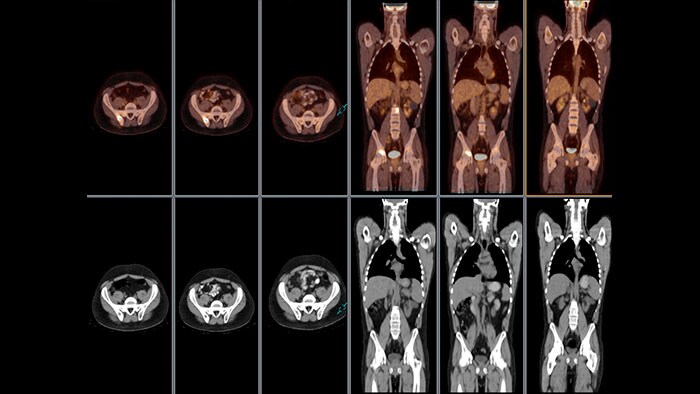

Generate new clinical insights

NM JETPack Application Suite for general MI includes a complementary set of organ-specific applications to meet the current and evolving needs of MI users, including endocrine, gastric, hepatobiliary, lung, neuro, renal, and whole-body and bone applications.

Streamline Molecular Imaging workflow

Offers comprehensive analysis and processing protocols for planar and SPECT studies including renal, lung, whole-body and bone, cardiac (first pass, shunt, and MUGA), gastric, esophageal, hepatobiliary, and endocrine applications.

NM Review provides a powerful MI and multi-modality image review and analysis environment for clinical evaluation of MI planar, SPECT, SPECT/CT, PET/CT, and PET/MR examinations.